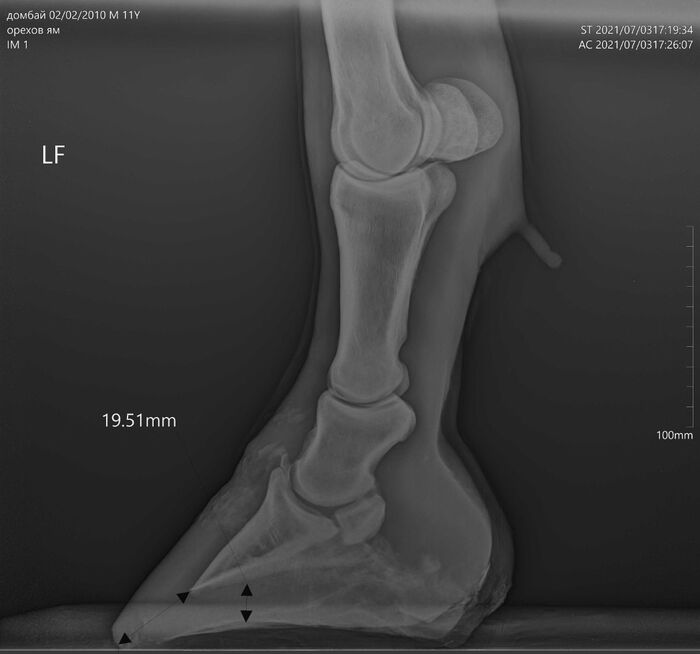

На этих x-ray снимках Домбай.

У него артроз (или артрит, я такой себе врач) пальчиков на руках.

Плюс косточка в копыте подходит очень близко к краю.

Из-за этого он все чаще и чаще страдает, иногда до коликов ( это когда от боли и стресса идет спазм ЖКТ и лошадь не может есть).